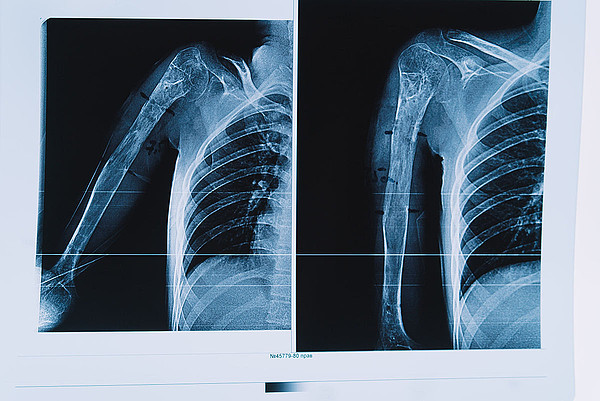

Кировские травматологи выполнили уникальную операцию по удлинению руки